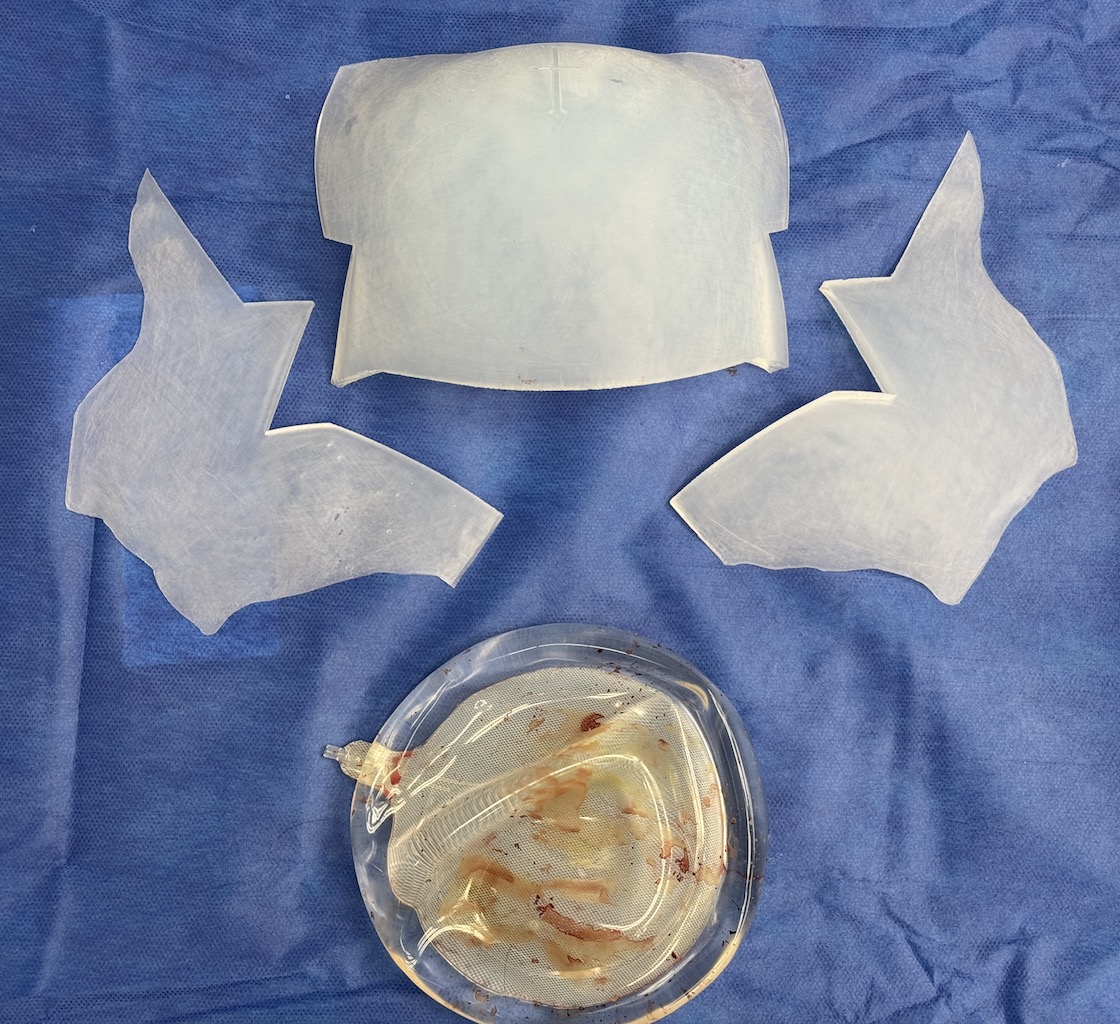

Desire for large overall skull augmentation procedure. Two piece custom skull implant designed with 250ccs volume.

1st stage scalp expander placed and inflated to 225ccs. 2nd stage two piece skull implant placed 4 months later.

Desire for large overall skull augmentation procedure. Two piece custom skull implant designed with 250ccs volume.

1st stage scalp expander placed and inflated to 225ccs. 2nd stage two piece skull implant placed 4 months later.